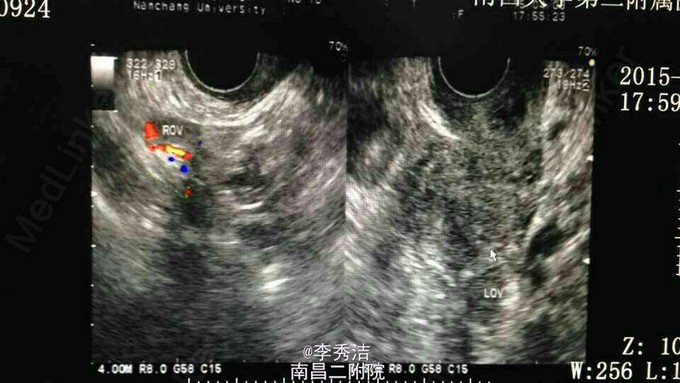

患者女,60岁,绝经10年余,发现血清 CA125升高10个月伴腰酸3个月。 妇检查发现左侧附件增厚,压痛明显。腹部彩超示肝右叶低回声结节。上腹部CT平扫示肝 S6段结节;左侧附件稍增大。血清 CA125 :511 CA125 。PETCT示左侧附件区结节装糖代谢异常增高灶,MT不除外。右侧肾上腺糖代异常增高占位,转移性MT首先考虑。右侧隔上、右侧盆腔糖代谢异常淋巴结。 行分段诊刮病理示:镜下粘液组织中见少于宫颈管粘膜,(子宫)镜下为粉染无结构物。抗炎一周后血清 CA125:1350.9 U/ml。后择期行腹腔镜探查术,术中探查:盆腔见少量血性分泌物,子宫表面散在芝麻大及绿豆大结节,双侧卵巢萎缩,形态正常,右侧输卵管形态正常,左侧输卵管壶腹部膨大增粗约1cm。决定行全子宫+双附件+左髂外增大的淋巴结切除术,术中冰冻切片示:(左侧输卵管)恶性肿瘤,上皮性癌, CA125 癌转移。术中进一步将盆腔淋巴结清扫干净,切除大网膜。外科医生探查肝肿瘤位于右肝脏面,切除之。术后石蜡切片病理报告示(左侧输卵管)浆液性乳头状腺癌。 患者于术后10天出院,后续进行化疗控制病情。